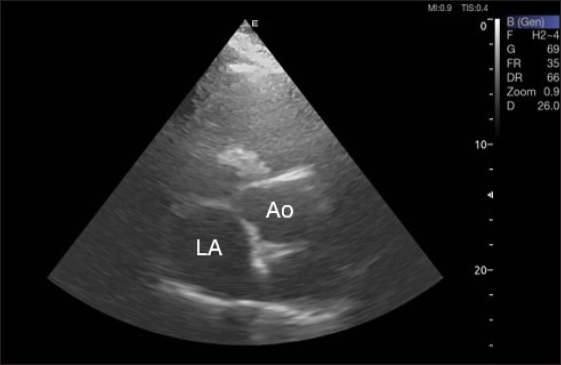

By positioning the probe perpendicularly in the fourth intercostal space or longitudinally in the fifth space with a little clockwise rotation, the interventricular septum, ventricles, and atria could be observed in the caudal long-axis four-chamber view (Fig. 1). From this vantage point, all camels could be seen to have a left ventricle, mitral valve, interventricular septum, right ventricle, and tricuspid valve. Figure 2 shows that in the short-axis image of the cardiac ventricles obtained with a little clockwise rotation at the 4th ICS, only the right ventricle, interventricular septum, and left ventricle were visible. Here, the dimensions of all camel heart were measured in M mode. The right parasternal two-dimensional short-axis pictures of the heart’s base in the first frame were used to determine the LA/Ao ratio, by applying 2D and M mode (Figs. 3 and 4). Despite some difficulties, we successfully acquired a pulmonary image by attempting to acquire the right ventricular outflow tract for the right short axis at the level of the great vessels.

Figure 5 shows an image of the ventricles, atria, and interventricular septum in the caudal long-axis four-chamber view acquired by positioning the probe perpendicularly in the fourth intercostal space or longitudinally in the fifth intercostal space with a little clockwise rotation. Every camel had a perfectly normal heart anatomy, including ventricles, tricuspid valve, mitral valve, and atria on both sides. During the fourth ICS image of the LVOT, the probe was turned slightly further cranially and twisted somewhat counterclockwise (Fig. 6). No camel is complete without an oblique aortic cross-section.

Fig. 3. Right parasternal short-axis view of 16 she-camel at great vessel level showing Ao=aorta and LA=left atrium.

Fig. 4. LA/Ao ratios for the right parasternal short axis of 18 racing camels at the great vessel level. Through the anatomical M mode.